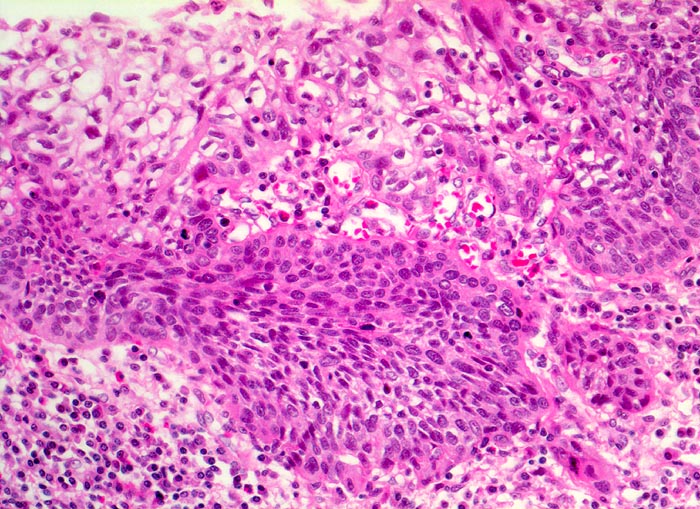

Carcinoma in situ der Ösophagusschleimhaut mit beginnender Invasion

Das schwer dysplastische Epithel bildet unregelmässige Zapfen, die in das Stroma vordringen. Fährt man an der Basis entlang, erkennt man an einer Stelle eine zipflige Tumorinvasion des Stromas. An dieser Stelle ist keine Basalmembran erkennbar. Die Submukosa enthält ein dichtes gemischtes Entzündungsinfiltrat.

Jahrelanger Nikotin- und Ethylabusus. Vor 6 Monaten ergab die Abklärung wegen progredienter Dysphagie ein inoperables stenosierendes Karzinom im distalen Ösophagus. Der Patient verstirbt am Tumorleiden.